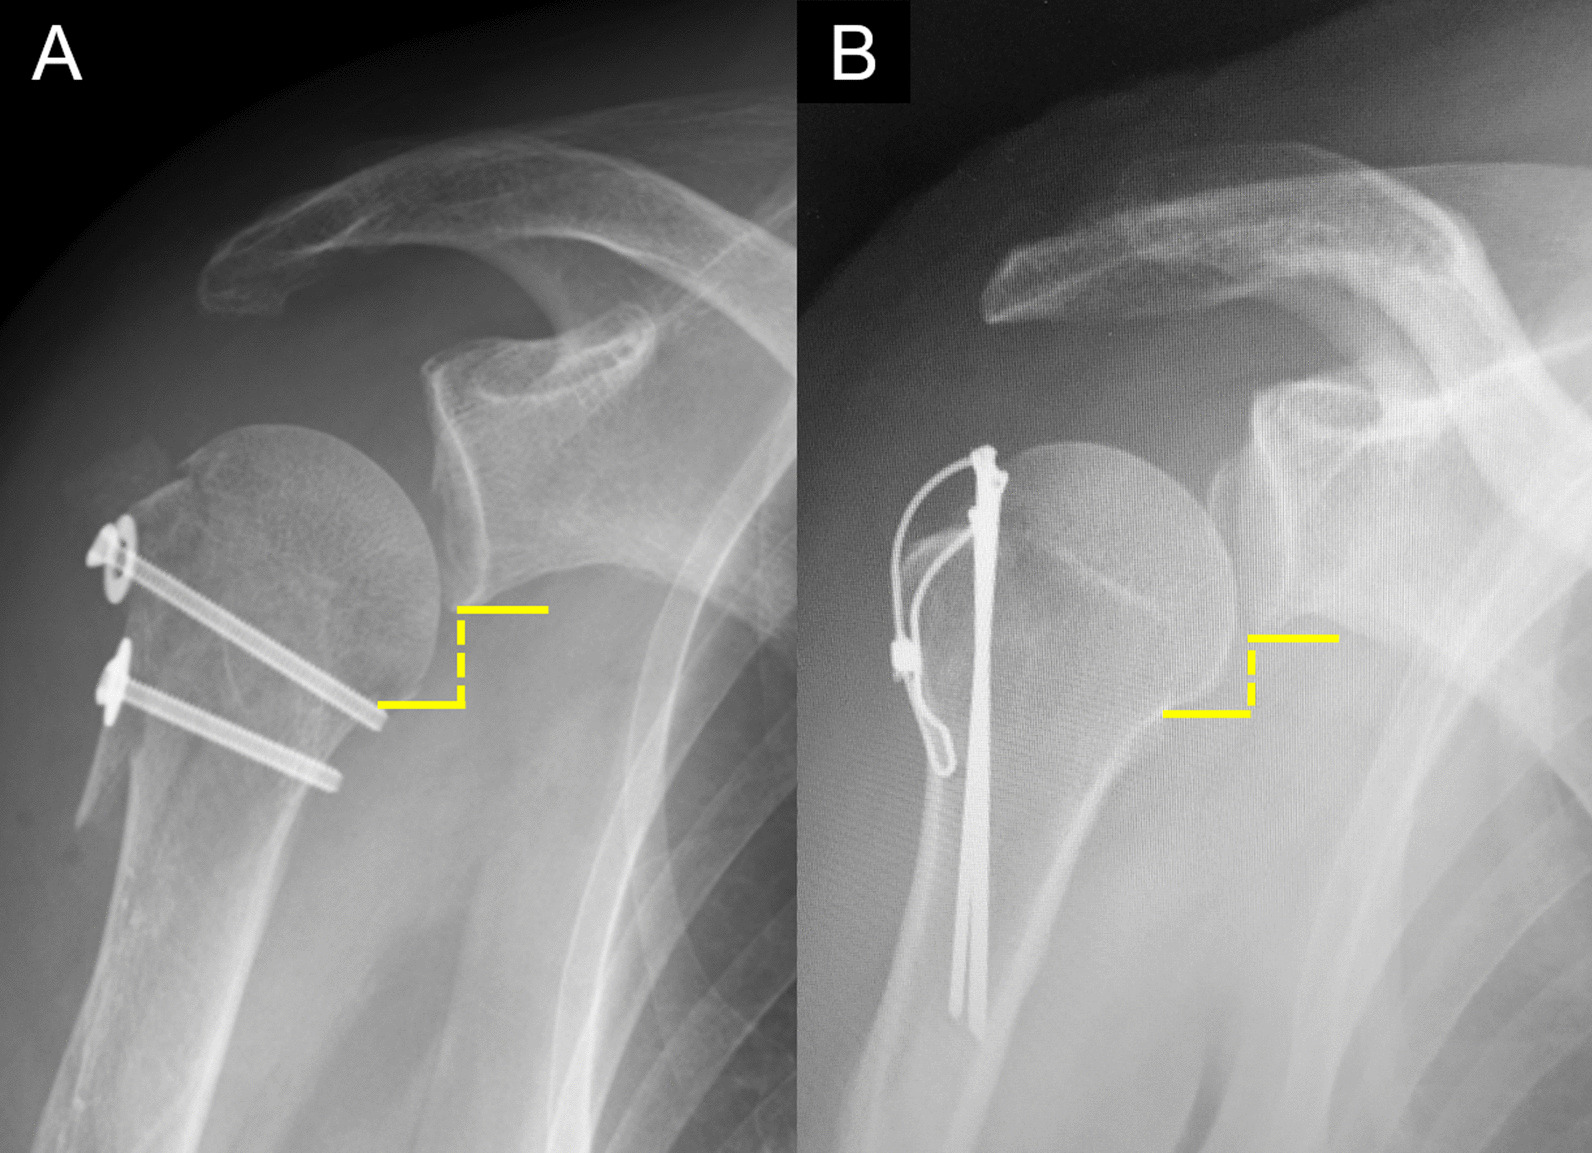

Various methods of humeral head inferior subluxation have been previously reported [3, 12, 13]. Carbone et al. define inferior subluxation as a distance of ≥ 1 cm between the humeral anatomical neck level and the glenoid inferior edge level [3]. We adopted this method for this study because a good intra- and excellent inter-rater reliability was reported [3]. Based on the previous studies [3, 13], plain radiographs of the shoulder in the upright position taken before surgery and at 1 week, 1 month, 3 months, and 6 months postoperatively were evaluated by one examiner. Inferior subluxation on the plain radiograph taken 1 week postoperatively was defined as inferior subluxation immediately after osteosynthesis, as previously described [2] (Fig. 1).

Fig. 1.

Radiographic assessment of inferior subluxation of the humeral head. A distance of ≥ 1 cm between the humeral anatomical neck level and the glenoid inferior edge level was defined as the presence of humeral head inferior subluxation. Postoperative radiograph images after surgery using a cannulated cancellous screw (A) or tension band wiring (B)